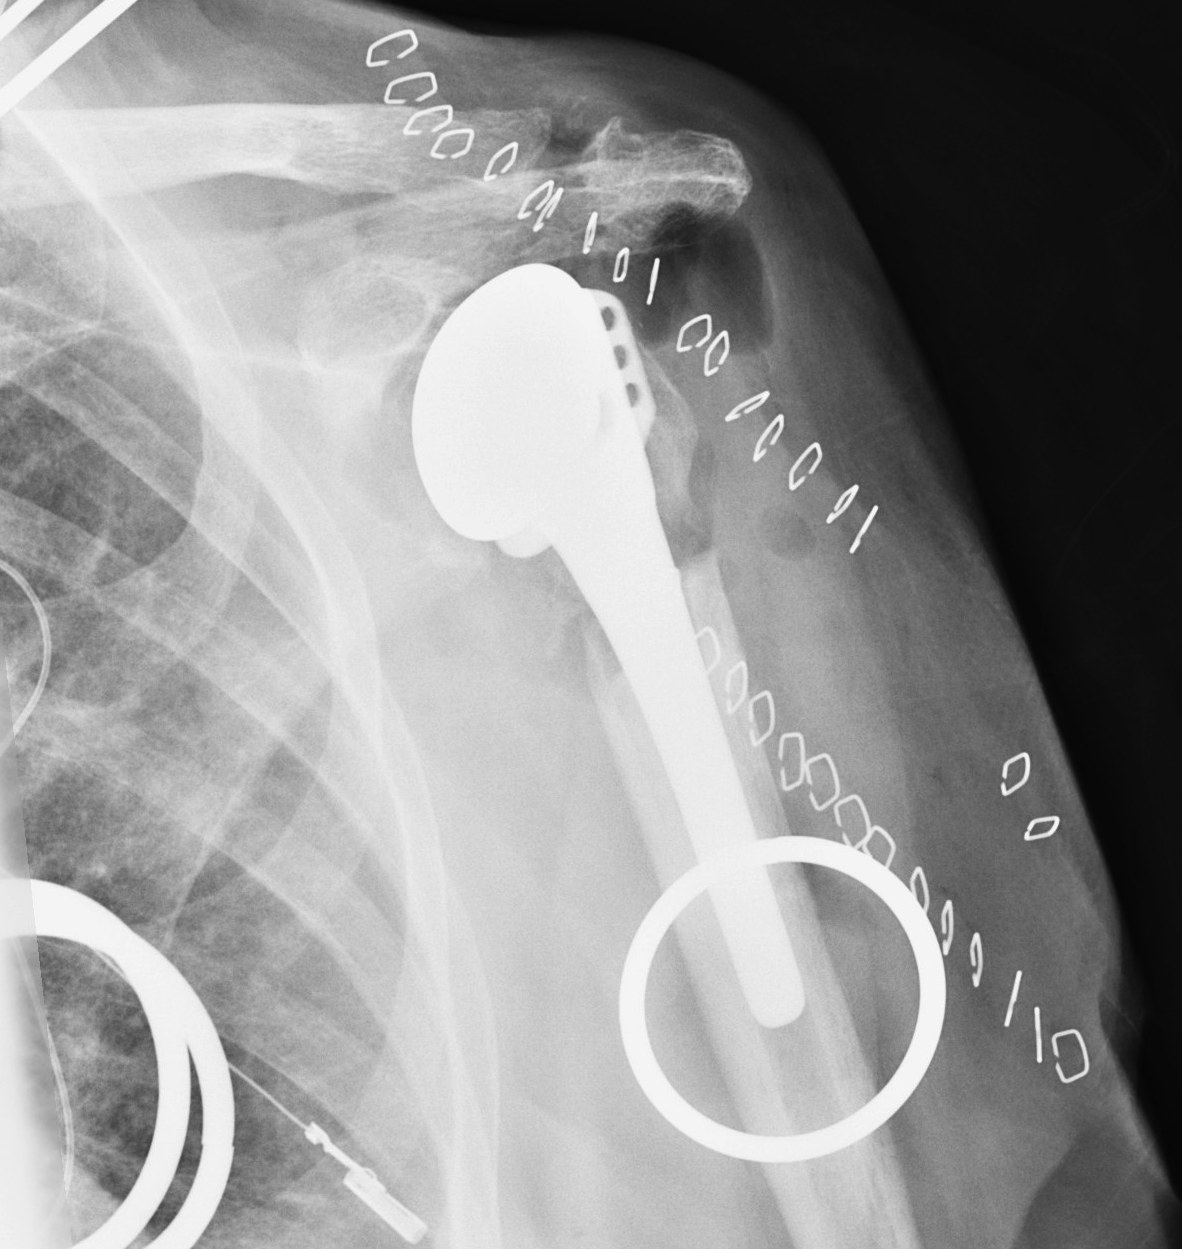

C.  Revision

- loose humeral prosthesis / osteolysis

Long stem > 2 cortical diameters past fracture

aTSA fracture 1aTSA fracture 2revTSA following fracturerevTSA for fracture